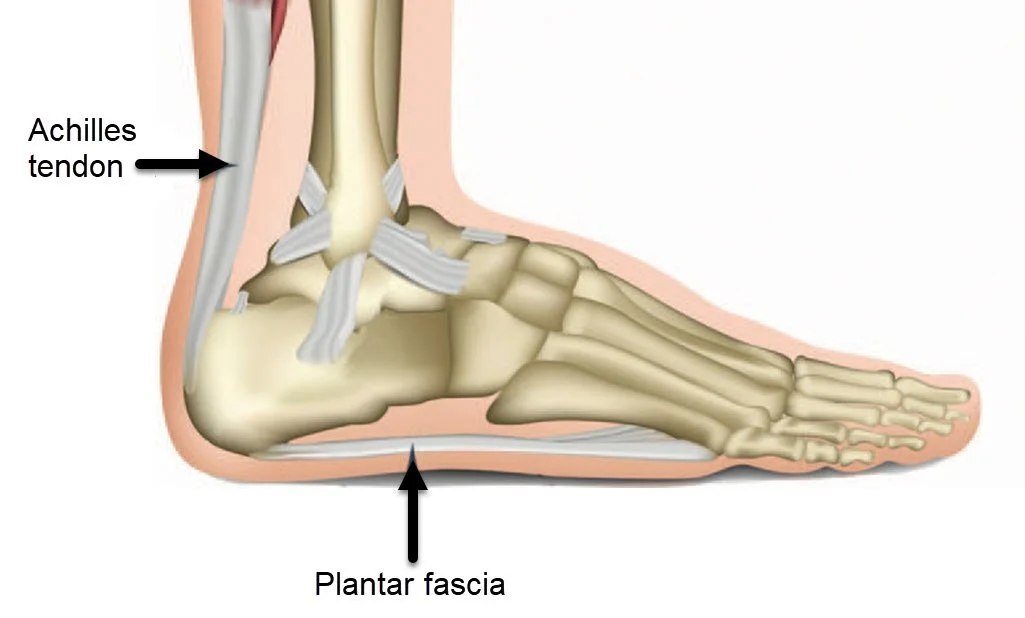

در پا چندین تاندون مهم وجود دارد، اما معروفترین آنها تاندون آشیل (Achilles tendon) است که عضلات ساق را به استخوان پاشنه متصل میکند. این تاندون قویترین تاندون بدن انسان است و نقش حیاتی در حرکات روزمره دارد. سایر تاندونها شامل تاندون تیبیال خلفی، پرونئال و اکستنسور هستند که هر کدام در ثبات و حرکت مچ و کف پا وظایف خاصی دارند.

تاندونهای پا در بخشهای مختلفی از کف و پشت پا تا انگشتان گستردهاند. مهمترین محلها عبارتند از:

تاندون آشیل: در پشت پا و بالای پاشنه قرار دارد.

تاندون تیبیال خلفی: در قسمت داخلی مچ و کف پا قرار گرفته و در حفظ قوس کف پا نقش دارد.

تاندون پرونئال: در بخش بیرونی مچ پا دیده میشود و به حرکت چرخشی پا کمک میکند.

تاندونهای اکستنسور: در قسمت رویی پا و انگشتان قرار دارند و وظیفه بلند کردن انگشتان را دارند.

شناخت محل دقیق هر تاندون برای تشخیص نوع آسیب اهمیت زیادی دارد، زیرا درد در هر ناحیه از پا میتواند به نوع خاصی از تاندون مربوط باشد.

تاندون پا در قسمتهای مختلف مچ، پاشنه و کف پا قرار دارد و عضلات را به استخوانها متصل میکند. معروفترین آن تاندون آشیل است که در پشت پاشنه دیده میشود.